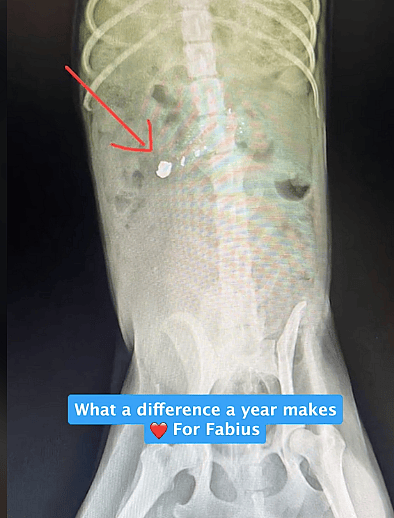

Days later, Fabius returned — but his condition shocked his rescuers. He was dragging his hind legs, and the team initially suspected he had been hit by a car, a common threat for street dogs in the area. However, an X-ray revealed a more horrifying truth: a bullet was lodged in his back.